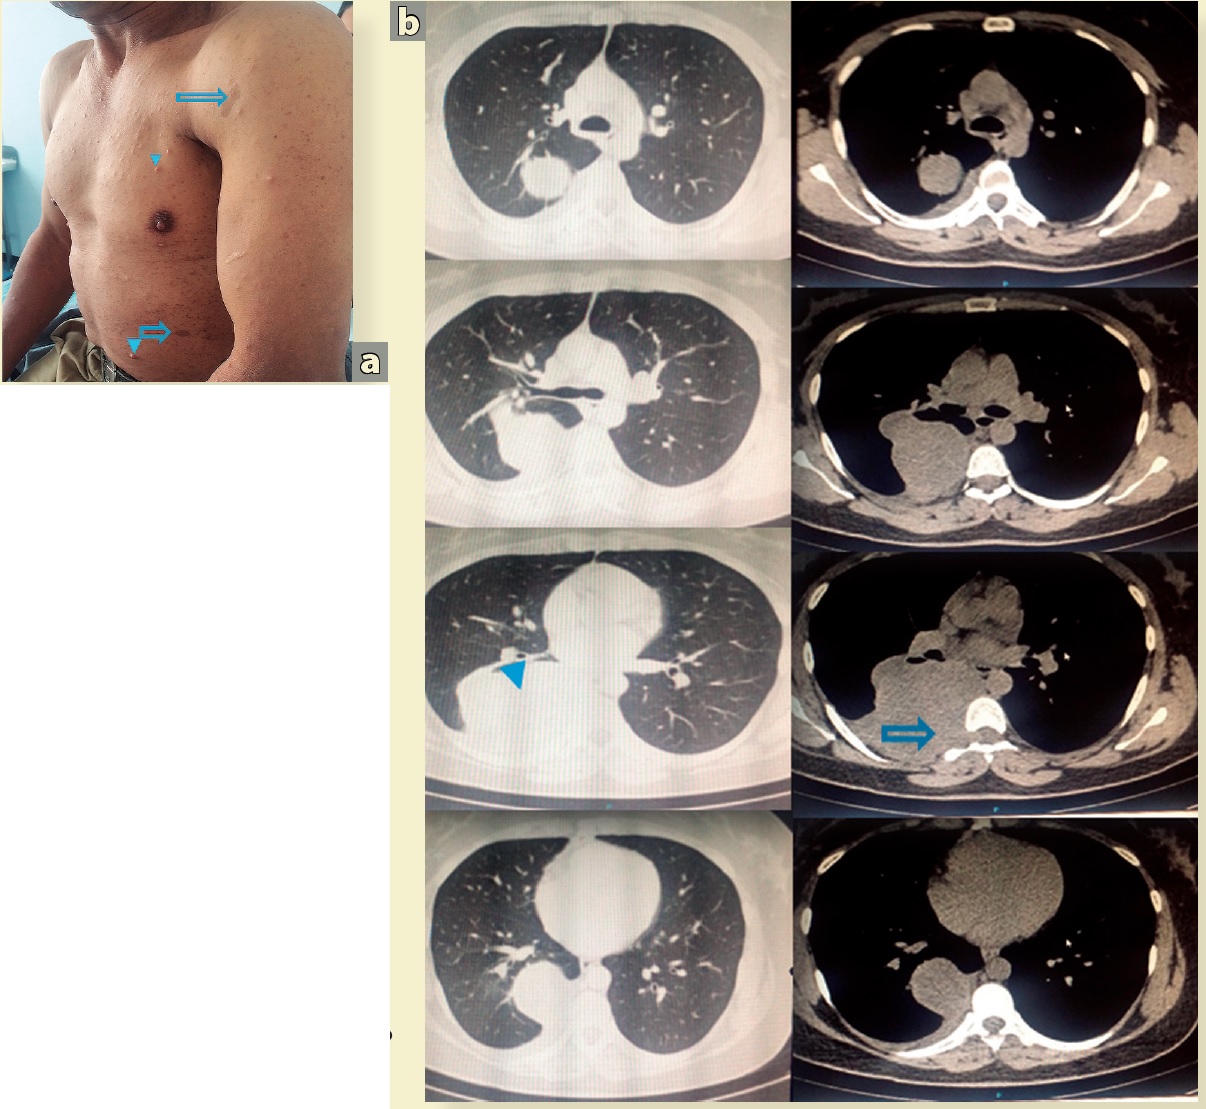

Hombre de 56 años, diagnosticado con neuro-fibromatosis diagnosticada en la adolescencia con algunos neurofibromas, ninguno mayor a 6 cm o que haya requerido resección quirúrgica previa. El único síntoma referido por el paciente, era parestesias de 2 años de evolución en la zona correspondiente al dermatoma de T6-T7 de creciente intensidad. a) Lesiones café con leche (flecha); algunos neurofibromas de pequeño tamaño (cabeza de flecha), b) Tomografia axial computarizada (TAC) simple de tórax. Lesión en pared torácica posterior derecha, desplazaste pulmonar (cabeza de flecha), invasor de la pleura parietal originado de la raíz nerviosa correspondiente al foramen transverso derecho de T6 (flecha). La biopsia guiada portomografía reportó un tumor maligno de la vaina del nervio periférico. El paciente fue llevado a toracotomía posterolateral derecha, con resección local amplia con fresado del foramen transverso y micro colgajo muscular sobre en la vértebra T6, para prevención de fistula de líquido cefalorraquídeo.

Figura 1 Hombre de 56 años, con neurofibromatosis y tumor de la vaina de nervio periférico de mediastino posterior.